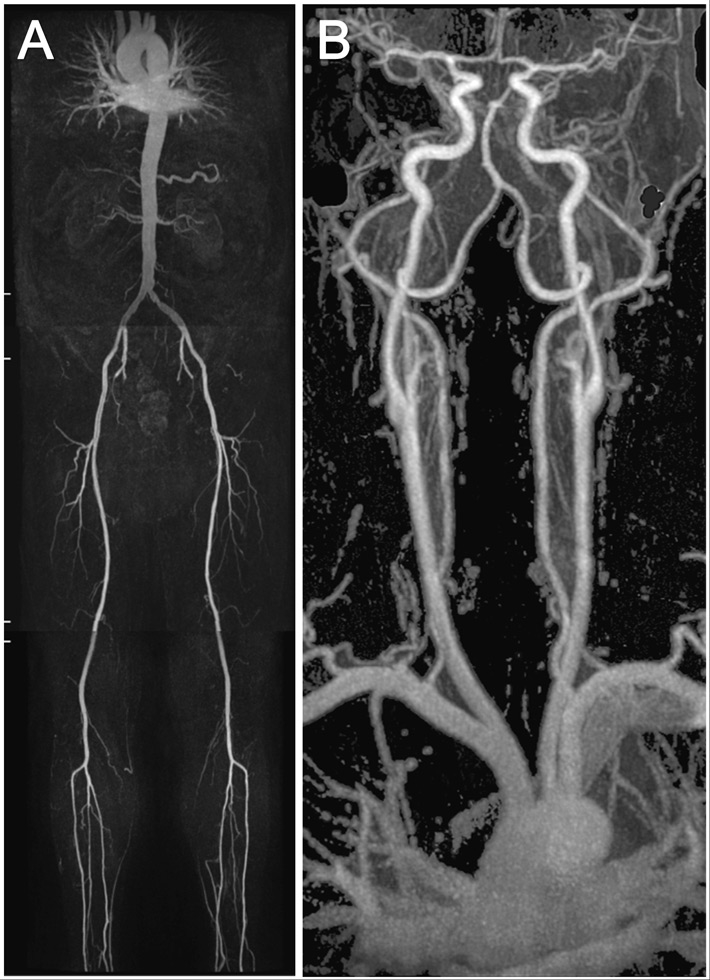

Figure 1

An example showing the MR whole body angiography.

The first part of the MR whole body angiography included thoracic/renal-, pelvis/thigh-, knee/calf-stations (A). The second part included the thoracic/carotid-station (B).

All MR angiography (MRA) examinations were performed on a 1.5-T whole-body MR system (Philips Achieva, Release 2.6, Philips Healthcare, Best, the Netherlands) with a gradient strength of 30 mT/m and a slew rate of 150 (mT/m/msec) according to previously described protocols [7, 8]. The scanning protocol involved a 2 step approach. The first part of the examination was in feet first, supine position, for the renal arteries down to the calf arteries with automatic table movement between the stations, using a 12-element phased-array peripheral vascular coil (Philips Healthcare). A biphasic intravenous administration of gadobenate dimeglumine with 0.15 mmol per kilogram of body weight at flow rates of 2.0 ml/sec followed by 0.033 mmol per kilogram of body weight at flow rates of 0.9 ml/sec, followed by a 30 mL saline flush at a flow rate of 0.8 ml/sec (fig. 1A). In the second part of the examination a 16 -element phased-array Neurovascular coil (Philips Healthcare) was used for the carotid and thoracic arteries in head first and supine position. An intravenous administration of gadobenate dimeglumine with 0.15 mmol per kilogram of body weight at flow rates of 1.5 ml/sec followed by a 30 ml saline flush at a flow rate of 1.5 ml/sec (fig. 1B).